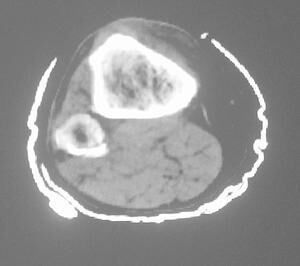

軟組織肉瘤(soft tissue sarcoma)是發(fā)生在結締組織的惡性腫瘤,包括皮下組織、肌肉、肌腱、血管、結締組織間隙以及空腔器官支柱基質等。現(xiàn)在治療該疾病的方法大多是放化療。副作用非常大,目前通過cls前沿生物治療技能聯(lián)合放化療或單獨使用,能將治療后的副作用降到較低。

手術是未轉移(擴散)的軟組織肉瘤的主要治療手段。為了確保癌癥不會復發(fā),對于我們來說,清除整個腫瘤及其周圍的器官或組織中可能有癌細胞是很重要的。

他們率先開發(fā)了控制軟組織肉瘤腫瘤的技能,無需切除(切除)四肢; 可以為超過十個病人中的九個做到這一點。新的重建技能使病人能夠在保持神經,血管和肌肉功能的同時執(zhí)行廣泛而復雜的操作。